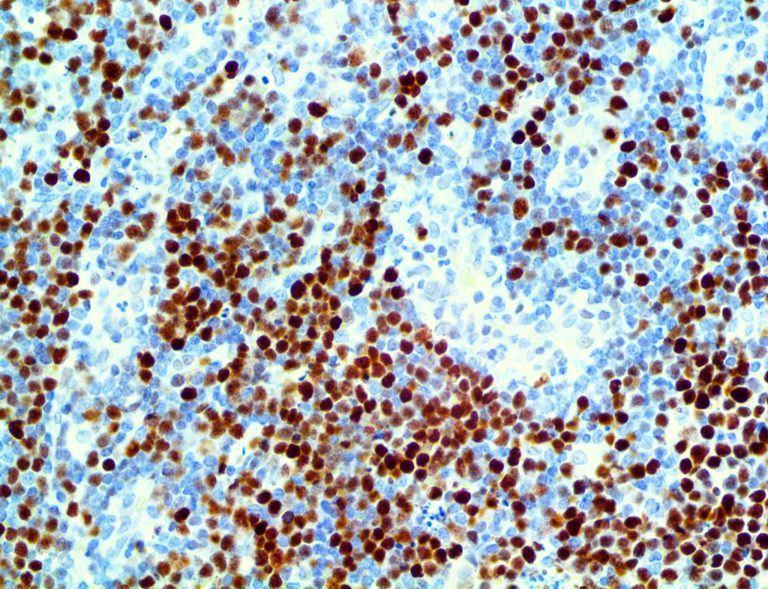

It is the ICU physician who is most likely to witness one of the deadliest manifestations of the abnormal immunological response, the cytokine storm syndrome (CSS). This response is also referred to by some as the cytokine release syndrome (CRS). CSS is characterized by continuous activation and expansion of macrophage and lymphocyte populations, which secrete large amounts of cytokines, causing the cytokine storm. This massive cytokine release is akin to hemophagocytic lymphohistiocytosis (HLH) disease, a syndrome characterized by initial unchecked and persistent activation of cytotoxic T lymphocytes and NK cells.

Clinical and laboratory manifestations of HLH include fever, enlarged liver and/or spleen, neurologic dysfunction, coagulopathy, liver dysfunction, cytopenias (i.e., low levels of erythrocytes, leukocytes, and/or platelets), hypertriglyceridemia, hyperferritinemia, hemophagocytosis, and eventually diminished NK cell activity as the immune system becomes progressively paralyzed. HLH can be familial (primary HLH) or secondary to another disease process (sHLH), such as rheumatic disease, in which it is referred to as macrophage activation syndrome (MAS, characterized by elevated ferritin).